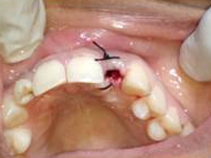

Punch Cut

Placement of Bone Grafting

After Punch Cut